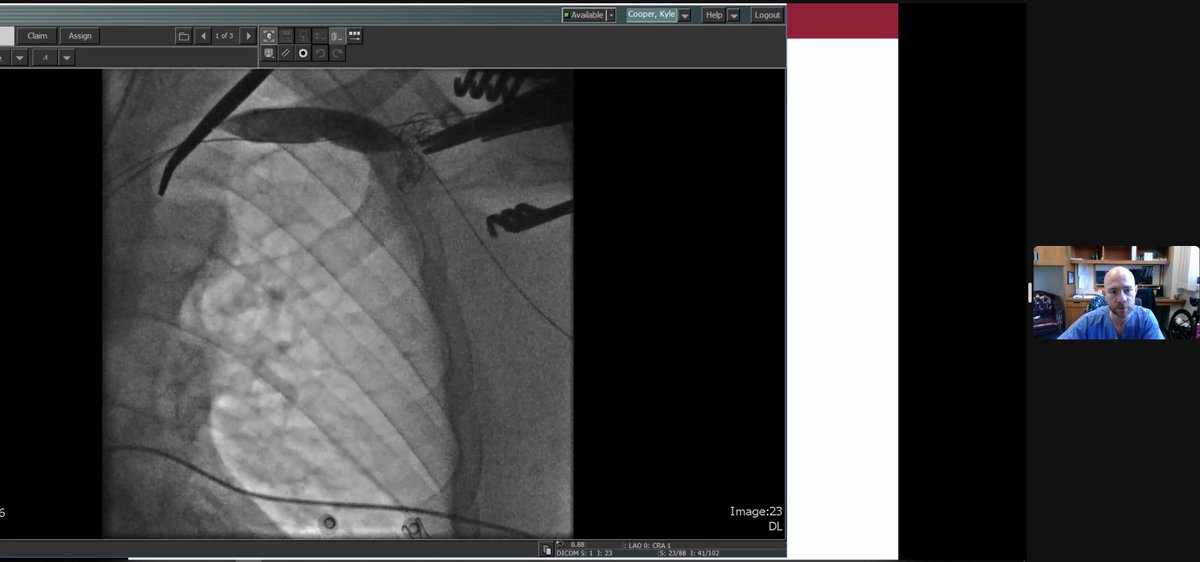

Beautiful Ischemic VT ablation mapped and ablated by Jalaj Garg utilizing #HDGrid. One-burn term achieved, utilizing 1. #EnsiteX nearfield detection algorithm with #Emphasismaps 2. #ILAM map achieved in VT with #lastdetection algorithm. #AbbottProud #OT Abbott Cardiovascular

Beautiful Ischemic VT ablation mapped and ablated by <a href="/drjalajgarg/">Jalaj Garg</a> utilizing #HDGrid. One-burn term achieved, utilizing

1. #EnsiteX nearfield detection algorithm with #Emphasismaps

2. #ILAM map achieved in VT with #lastdetection algorithm.

#AbbottProud #OT <a href="/AbbottCardio/">Abbott Cardiovascular</a>